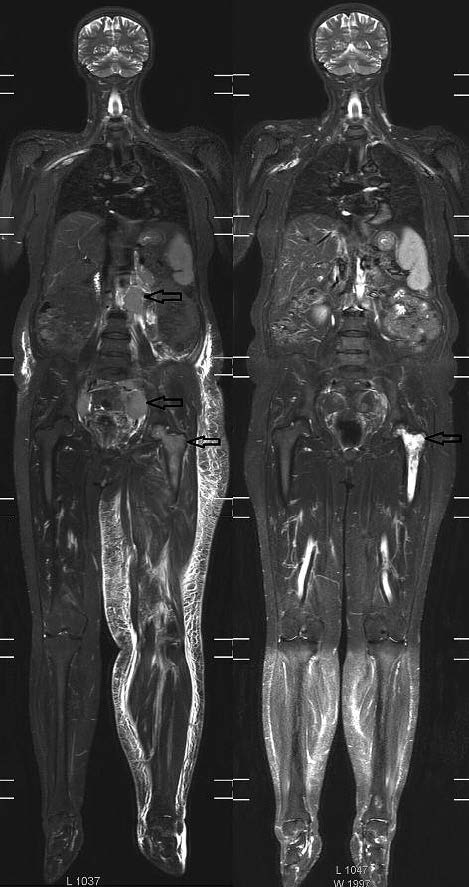

Шести из 15 пациентов после 4 курсов противоопухолевой терапии повторно выполнено КТ, МРТ-ДВИ-ВТ и ПЭТ/КТ. У 4 (из 6) больных достигнуто значительное сокращение размеров опухоли (не менее 80% от исходных размеров). Примеры визуализации динамики уменьшения размеров опухоли представлены на рис. 1, 2.

Рис. 1. Диффузионно-взвешенные изображения (проекция максимальной интенсивности, MIP) методом МРТ-ДВИ-ВТ больной с ФЛ до (слева) и после (справа) проведения 4 курсов ПХТ.

Стрелками указаны конгломераты увеличенных лимфатических узлов. После 4 курсов ПХТ определяется регресс конгломератов лимфатических узлов.